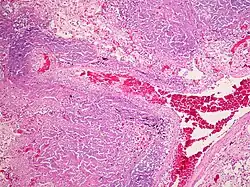

A Tuberculose miliar ou tuberculose cutânea aguda disseminada é uma classificação médica internacional para um agravamento da tuberculose por sua ampla difusão dentro do corpo humano gerando pequenas lesões na pele (de 1 a 5mm).[1]

Essa infecção bacteriana crônica e contagiosa geralmente causada por Mycobacterium tuberculosis que se espalhou para outros órgãos do corpo, através do sangue ou do sistema linfático. TB miliar pode infectar qualquer número de órgãos, frequentemente afetando os pulmões, as meninges, o fígado e o baço. É uma complicação grave de cerca de 1 a 3% dos casos de tuberculose.

Infecções tuberculosas generalizadas frequentemente causam alterações inespecíficas nos exames laboratoriais de rotina, podendo passar despercebidas em uma radiografia de tórax, sendo assim recomendado o exame de material obtido por punções, procedimentos cirúrgicos ou necropsias.[2]